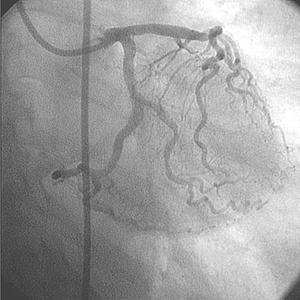

Diagnóstico

• La angiografía inicial mostró una arteria coronaria derecha pequeña no dominante

• La DA presentaba una enfermedad leve.

• La arteria circunfleja mostraba 90% de estenosis.

• La función ventricular izquierda era normal.

Tratamiento de la circunfleja

• Se colocó un catéter guía adecuado para facilitar el posible uso de varios dispositivos intervencionistas.

• Se usó una cuerda guía para cruzar la lesión en la arteria circunfleja.

• Se intentó sin éxito la dilatación de la lesión con un balón de 4,0 mm × 20 mm.

• Se intentó sin éxito la dilatación de la lesión con balón de 4,0 mm × 15 mm a 14 ATM.

• Tampoco se obtuvo éxito en expandir la lesión con un balón de 4,0 mm × 20 mm a 14 ATM.

• Se utilizó balón de corte Flextome™ de 4,0 mm × 10 mm, sin éxito.